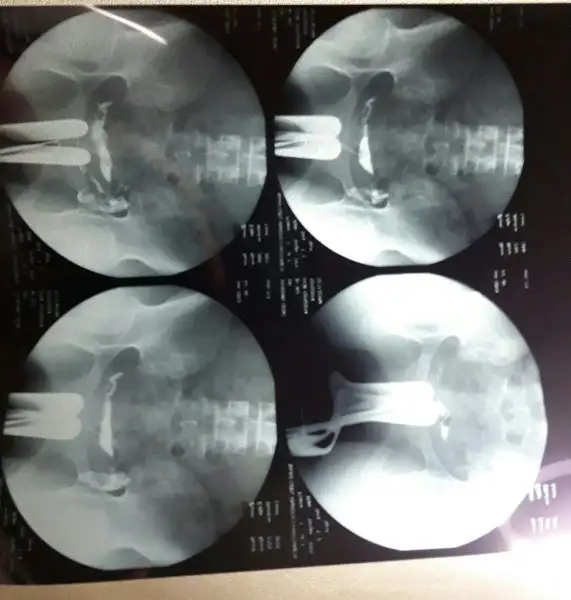

Ay herkesin rahmi ne kadar da farklı neresi neresi çözmek için 5 dakika baktım resme evire çevire. tüplerin açık onu anladım ama rahim arkaya doğru yatmış ya galiba , yapışıklık vs var mı yok mu hiç anlamadımKızlar yükledim sonunda yorumlarmısınız

Aynen bende oyle dusundum Rabbim farklı farklı yaratmışAy herkesin rahmi ne kadar da farklı neresi neresi çözmek için 5 dakika baktım resme evire çevire. tüplerin açık onu anladım ama rahim arkaya doğru yatmış ya galiba , yapışıklık vs var mı yok mu hiç anlamadım

Bak cnm rahmin şekilleri yandan bakılınca ilk resim normal olanı seninki bence 3. Resme benziyor retroflexed rahimAynen bende oyle dusundum Rabbim farklı farklı yaratmış

2 küçük siyahlığın üstündeki büyük siyahlığı diyorsun değil mi? leğen kemiğinin ortasındaki boşluk o. bebeğin çıktığı yer yani. açıya göre öyle farklı çıkmış olabilir ama çatın dar olayı burdan anlaşılıyor.xpreiaZ siyah boşluk karın içi boşlugu mu ne? Yasemin in dar uzın benimki cok geniş bide benim rahim çok yukarda sanki yaseminin ki asagıda

Sen yine anliyosun ben hic anlamiyorum rahim hangisi tupler neresi acik olduğunu nere anliyosunuz hiç bilmiyorum nasil arkaya yatmış kiAy herkesin rahmi ne kadar da farklı neresi neresi çözmek için 5 dakika baktım resme evire çevire. tüplerin açık onu anladım ama rahim arkaya doğru yatmış ya galiba , yapışıklık vs var mı yok mu hiç anlamadım